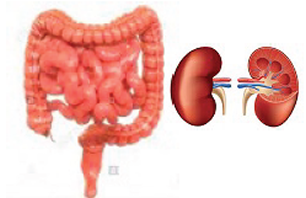

Cuando se consume suficiente agua, se puede retrasar el envejecimiento y mejorar enfermedades, como diabetes, hipoglucemia, artritis, sequedad cutánea y obesidad. Los riñones son los órganos que ayudan al cuerpo a eliminar residuos y necesitan suficiente agua para hacer su trabajo de depuración en el intento de mantenerlo limpio.

El colon o intestino grueso, es la porción final del tracto digestivo humano. Se encarga de eliminar los desechos del cuerpo. En un colon sano y en condiciones normales, viven bacterias “amigables” que sintetizan valiosos nutrientes como las vitaminas 'K' y partes del complejo “B”.

El colon, los riñones, los pulmones y la piel, son los responsables de la eliminación de los desechos del cuerpo. El funcionamiento correcto del colon es esencial para mantener una buena salud. Muchos de nuestros problemas crónicos de salud, provienen de una disfunción intestinal.